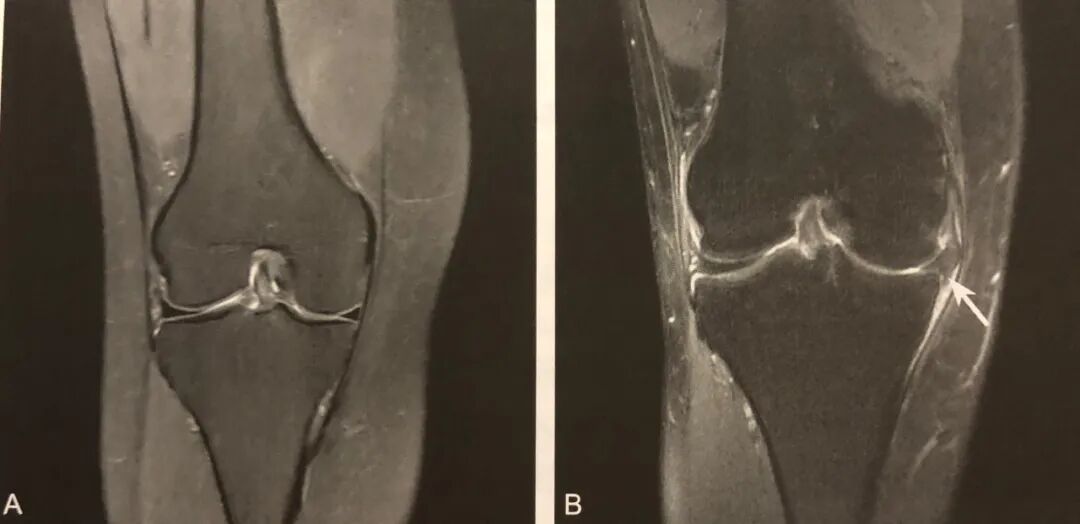

1. 半月板移位的直接征象;

2. 在膝关节 MRI 冠状位半月板体部的中央平面观察;

3. 半月板外缘超过胫骨平台关节面边缘 ≥3mm ;

4. 常伴半月板复杂撕裂或膝关节支持系统损伤,应注意观察。